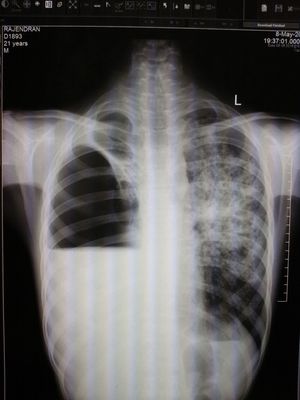

Abcent rt lung , rt lung dysplasia é (pleural effusion , big abcess or cyst). Lt lung fibrosis or intistitial lung disease

Pleural effusion right lung. And interstetial fibrosis or pneumonitis in left lung.

🧐getting a diagnosis from the plain radiograph only is definitely tricky. Right lung show pleural effusion(pleural disease) and air trapping (bronchial disease) with upper lobe collapse. Left lung gives an impression of hyper inflation with patchy infiltrates in upper lobe (parenchymal disease) a c t scan of the chest may give better evaluation

Tb left side (milliary patern) , right side fibrosis plus haemo-neumotorax 50% aprox